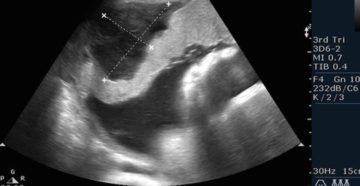

11 неделя беременности Развивающаяся беременность на 11 неделе приносит ощутимые перемены в тело женщины и…

11 неделя беременности: что происходит с малышом и мамой, признаки осложнений, необходимые анализы + отзывы…

11 неделя беременности: что происходит в организме женщины и с плодом, исследования и осложнения на…

11 неделя беременности: развитие крохи и токсикоз гудбай Здравствуйте, дорогие читательницы! Совсем скоро завершится 1…